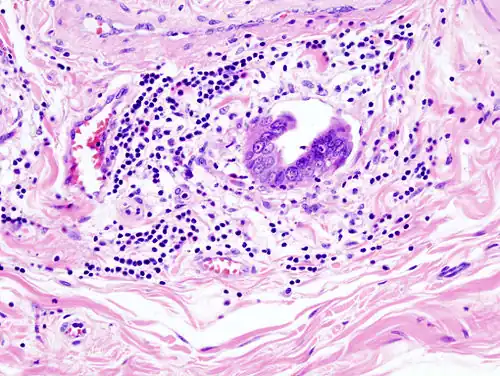

-

Gallbladder adenocarcinoma lymphatic invasion histopathology -

Incidentally discovered gallbladder cancer (adenocarcinoma) following a cholecystectomy. -

Gallbladder adenocarcinoma histopathology